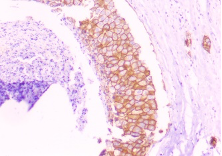

HISTOPATHOLOGY

Fig shows an endoscopic biopsy from a 54 year old individual. Identify the anatomical part of the intestine. What is the pathology. With what clinical symptoms do these patients present? (see surface epithelium)